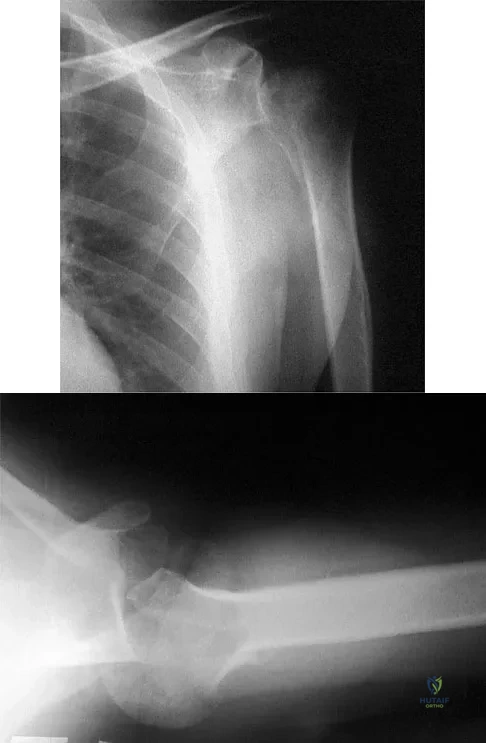

Question 72

A 25-year-old left hand-dominant man has severe left shoulder pain after being involved in a high-speed motor vehicle accident. Examination reveals that he is unable to move the left shoulder. His neurovascular status is intact in the entire left upper extremity. A radiograph is shown in Figure 19. What is the most appropriate surgical management of this injury?

Explanation